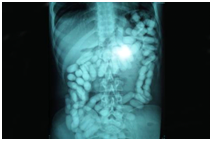

Carrying these packages comes with two health risks; primarily the drug mule may experience gastrointestinal obstruction or perforation and secondly, most dangerously; the packages can rupture within the body and lead to fatal toxicity and death.41 Capsules which are swallowed are required to be concealed for at least a day, whereas inserted packages are for short travel times. Heroin is still found to be one of the most common substances contained within capsules of body packers. The drug mules will go to the extent of taking anti diarrhea medication to prevent the passing of the capsules.42 Common signs of identification of such drug mules have been detected, yet in many cases, experienced drug mules and smaller airports will miss these signs and the drugs will pass into the destination undetected. Suspicion may arise when forming a link between the origin of the individual and the destination; this may be followed by their declaration of travel being vague or doubtful. Other physical signs may be the lack of mobility whilst sitting and an odor from the mouth as a result of the gastric acid on the packets concealed.41 If drug mules are traveling on a long-haul flight and refuse to eat during this time, the passenger will be notified to security, as this is common to prevent the passing of the illicit substances. The appearance of a mule may be nervous, with shaking of the body due to a combination of hunger and anxiety along with perspiration and uneasy walking due to the body cavity discomfort. If any signs are detected and deemed suspicious, the individual will undergo an in depth full body x-ray as Figure 8 shows.42,43 This demonstrates the desperate measures being taken to ensure the cycle of the trade of drugs such as heroin continues, due to its vital role in fueling the economy and the addiction.

Figure 8 Body cavity x-ray of a suspected smuggler who swallowed 134 capsules.43